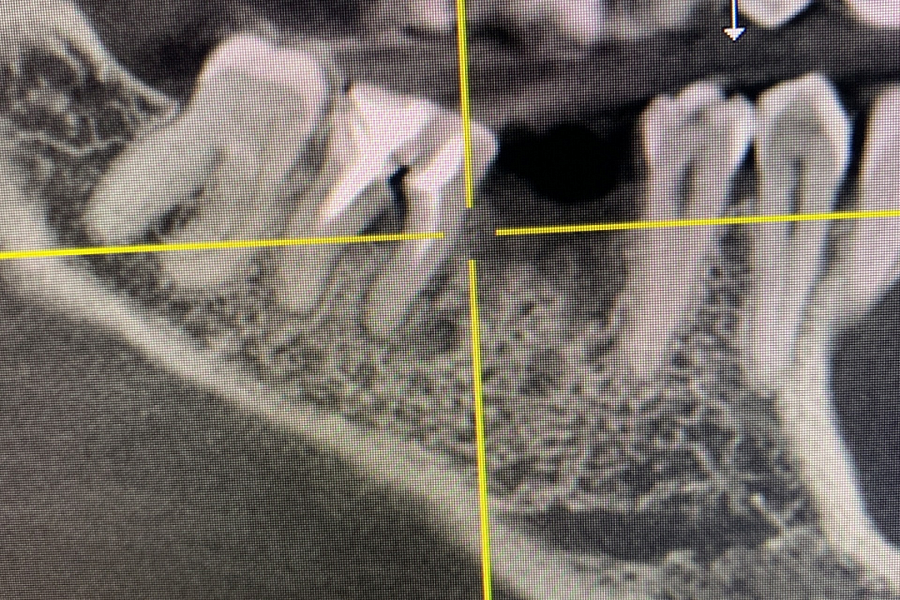

Пациентка обратилась с жалобой на перелом зуба, который ощутила при накусывании.

Провели имплантацию при помощи хирургического шаблона, который позволяет максимально точно спроектировать и спозиционировать положение имплантата для будущей функциональной нагрузки, грамотного распределения давления на имплантаты, а также здоровья зубного импланта. Операция прошла успешно.